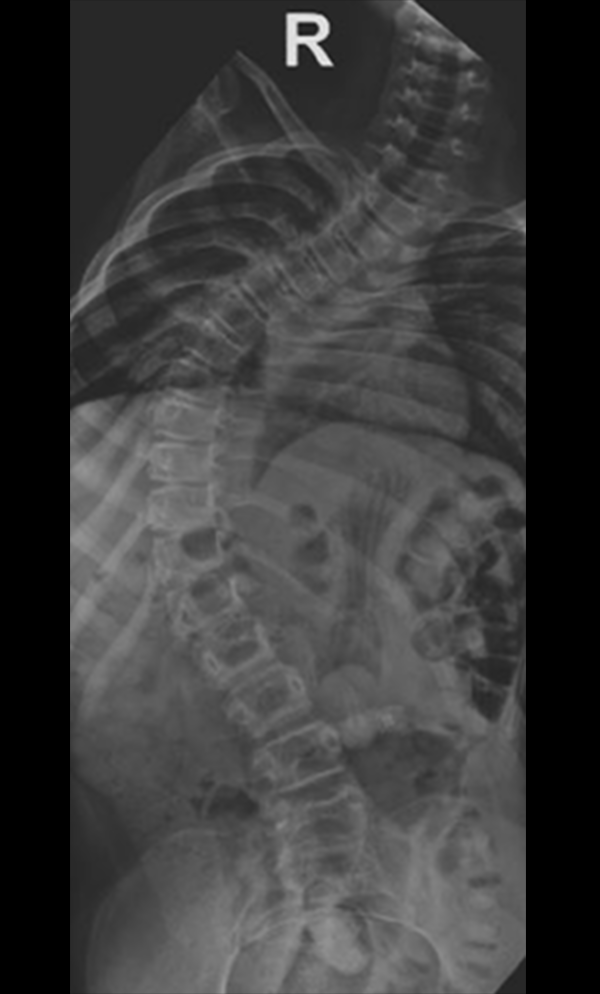

Gallery : Before - After